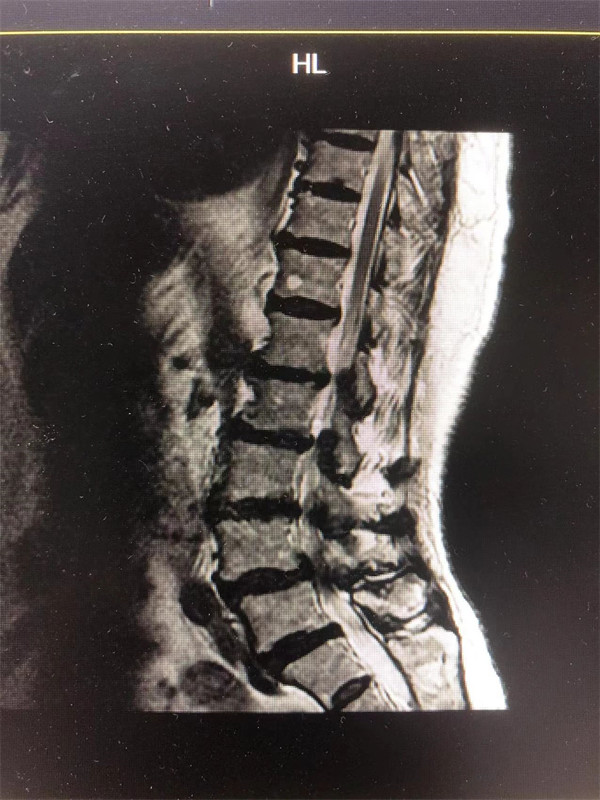

戈主任仔細(xì)詢問(wèn)阿婆病情癥狀,綜合查體及MRI片情況,認(rèn)為阿婆有明顯的腰椎滑脫,腰椎管狹窄,這是引發(fā)阿婆病痛的主要因素。

手術(shù)前↓